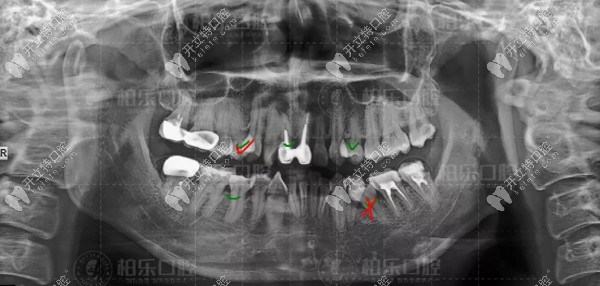

口腔檢查牙齒情況▲口腔檢查牙齒情況

去到醫(yī)院做了牙片,從牙片上很明顯可以看出,我的兩顆門牙是假牙,兩顆大牙做過根管治療,還有三顆大牙做了牙冠。

我才28歲,牙齒修修補(bǔ)補(bǔ)滿口亂牙,想想就心塞。

口腔檢查我的牙片

▲口腔檢查我的牙片